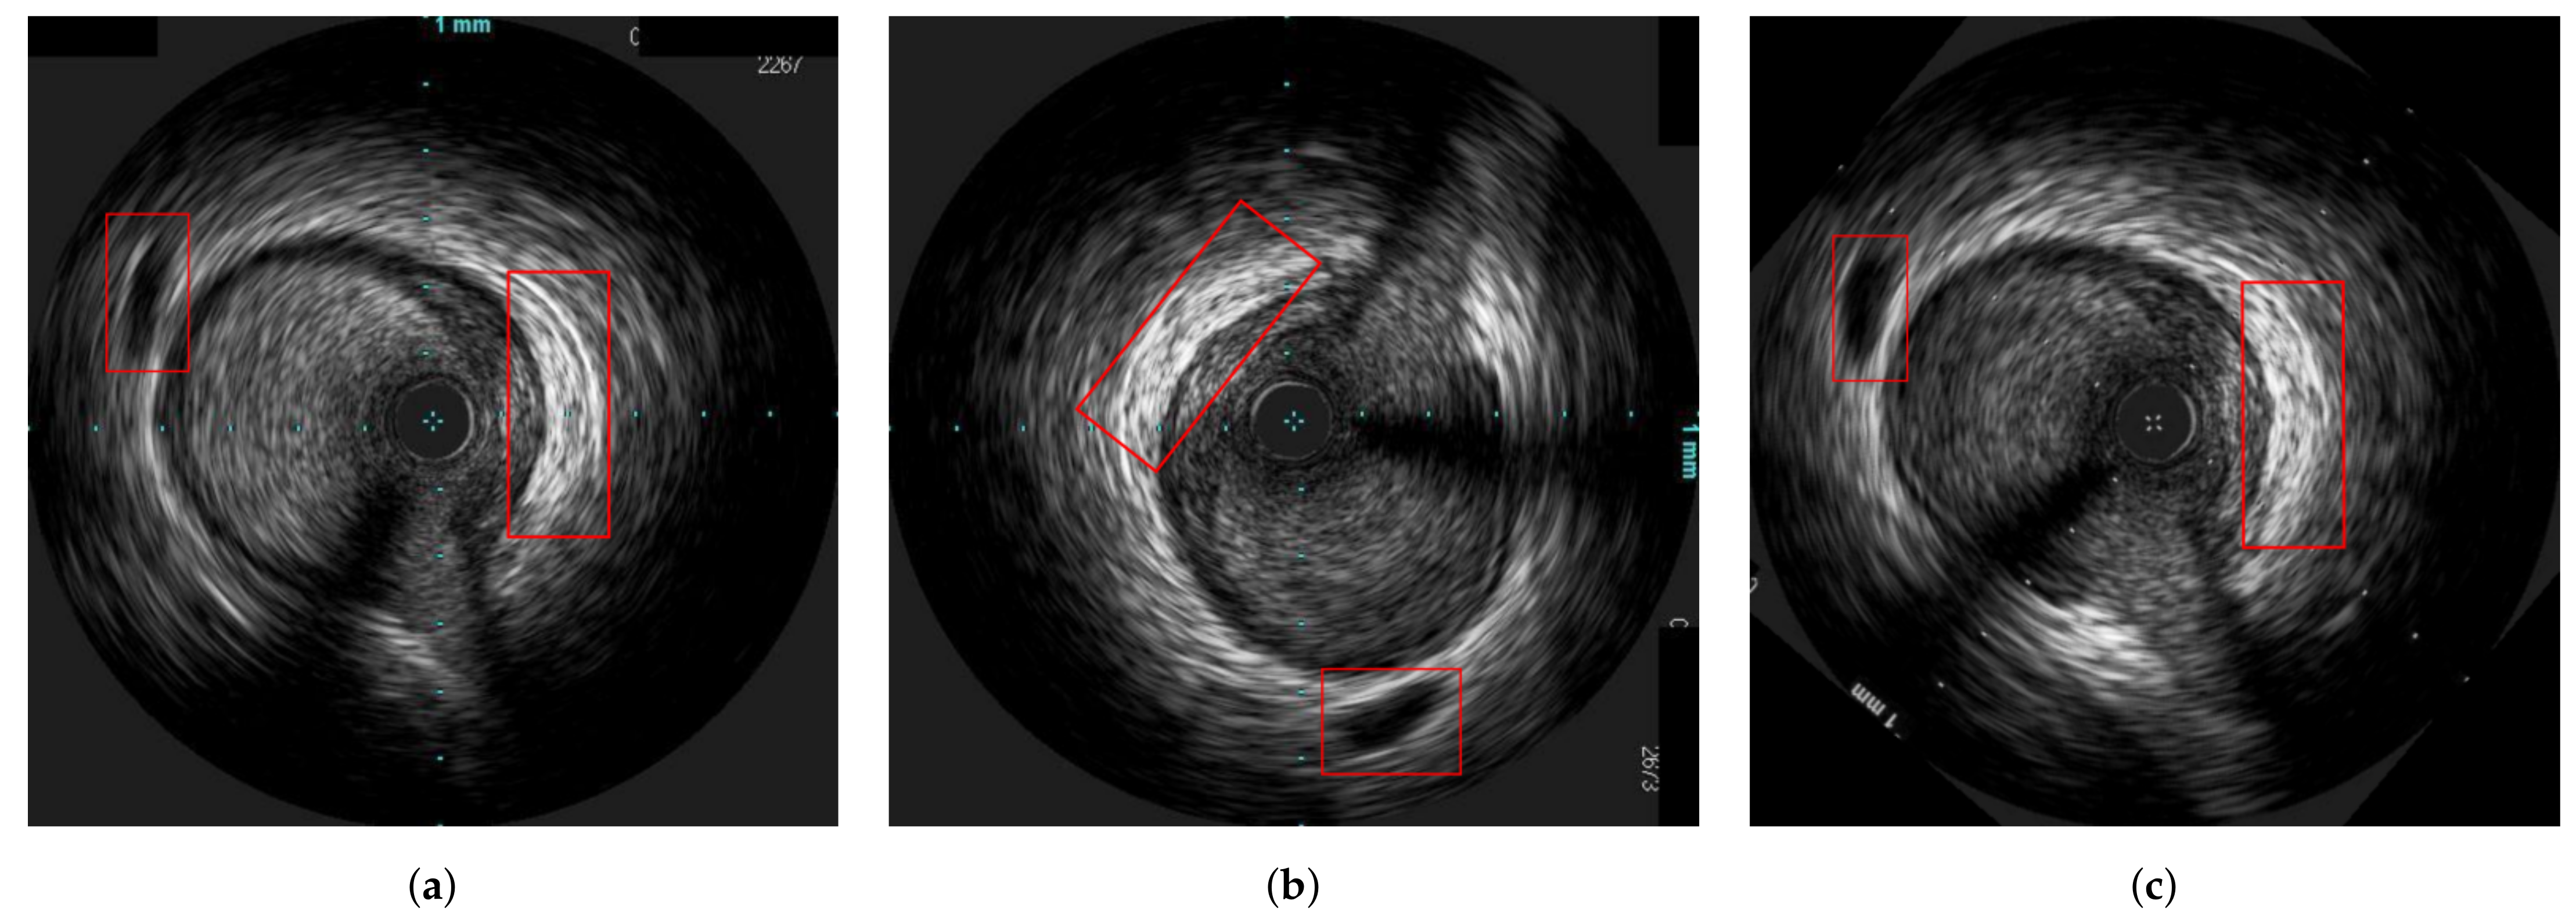

3.3. Axial Registration

- Rigid distortion, by randomly translating and rotating an image to simulate the circumferential movement of the probe. The rotation range was , the translation range is pixels and both are sampled based on the uniform distribution.

4.2. Experiments on In-Vivo Data